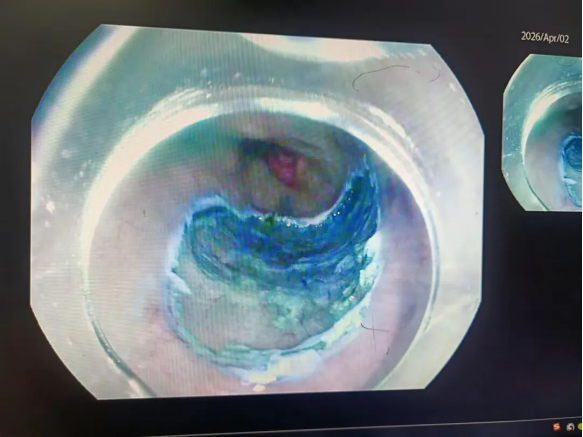

经过充分的术前准备与沟通,商南县医院消化内科团队在内镜下依次完成染色、精准标记病变位置、注射针注射、电刀剥离等操作,成功剥离食道癌前病变黏膜。手术全程采用微创方式,最大程度保留了食管的正常结构与功能。术后患者生命体征平稳,自述无身体不适,恢复状况良好。病理检查进一步确认病变已完整切除,达到根治效果。

术后创面